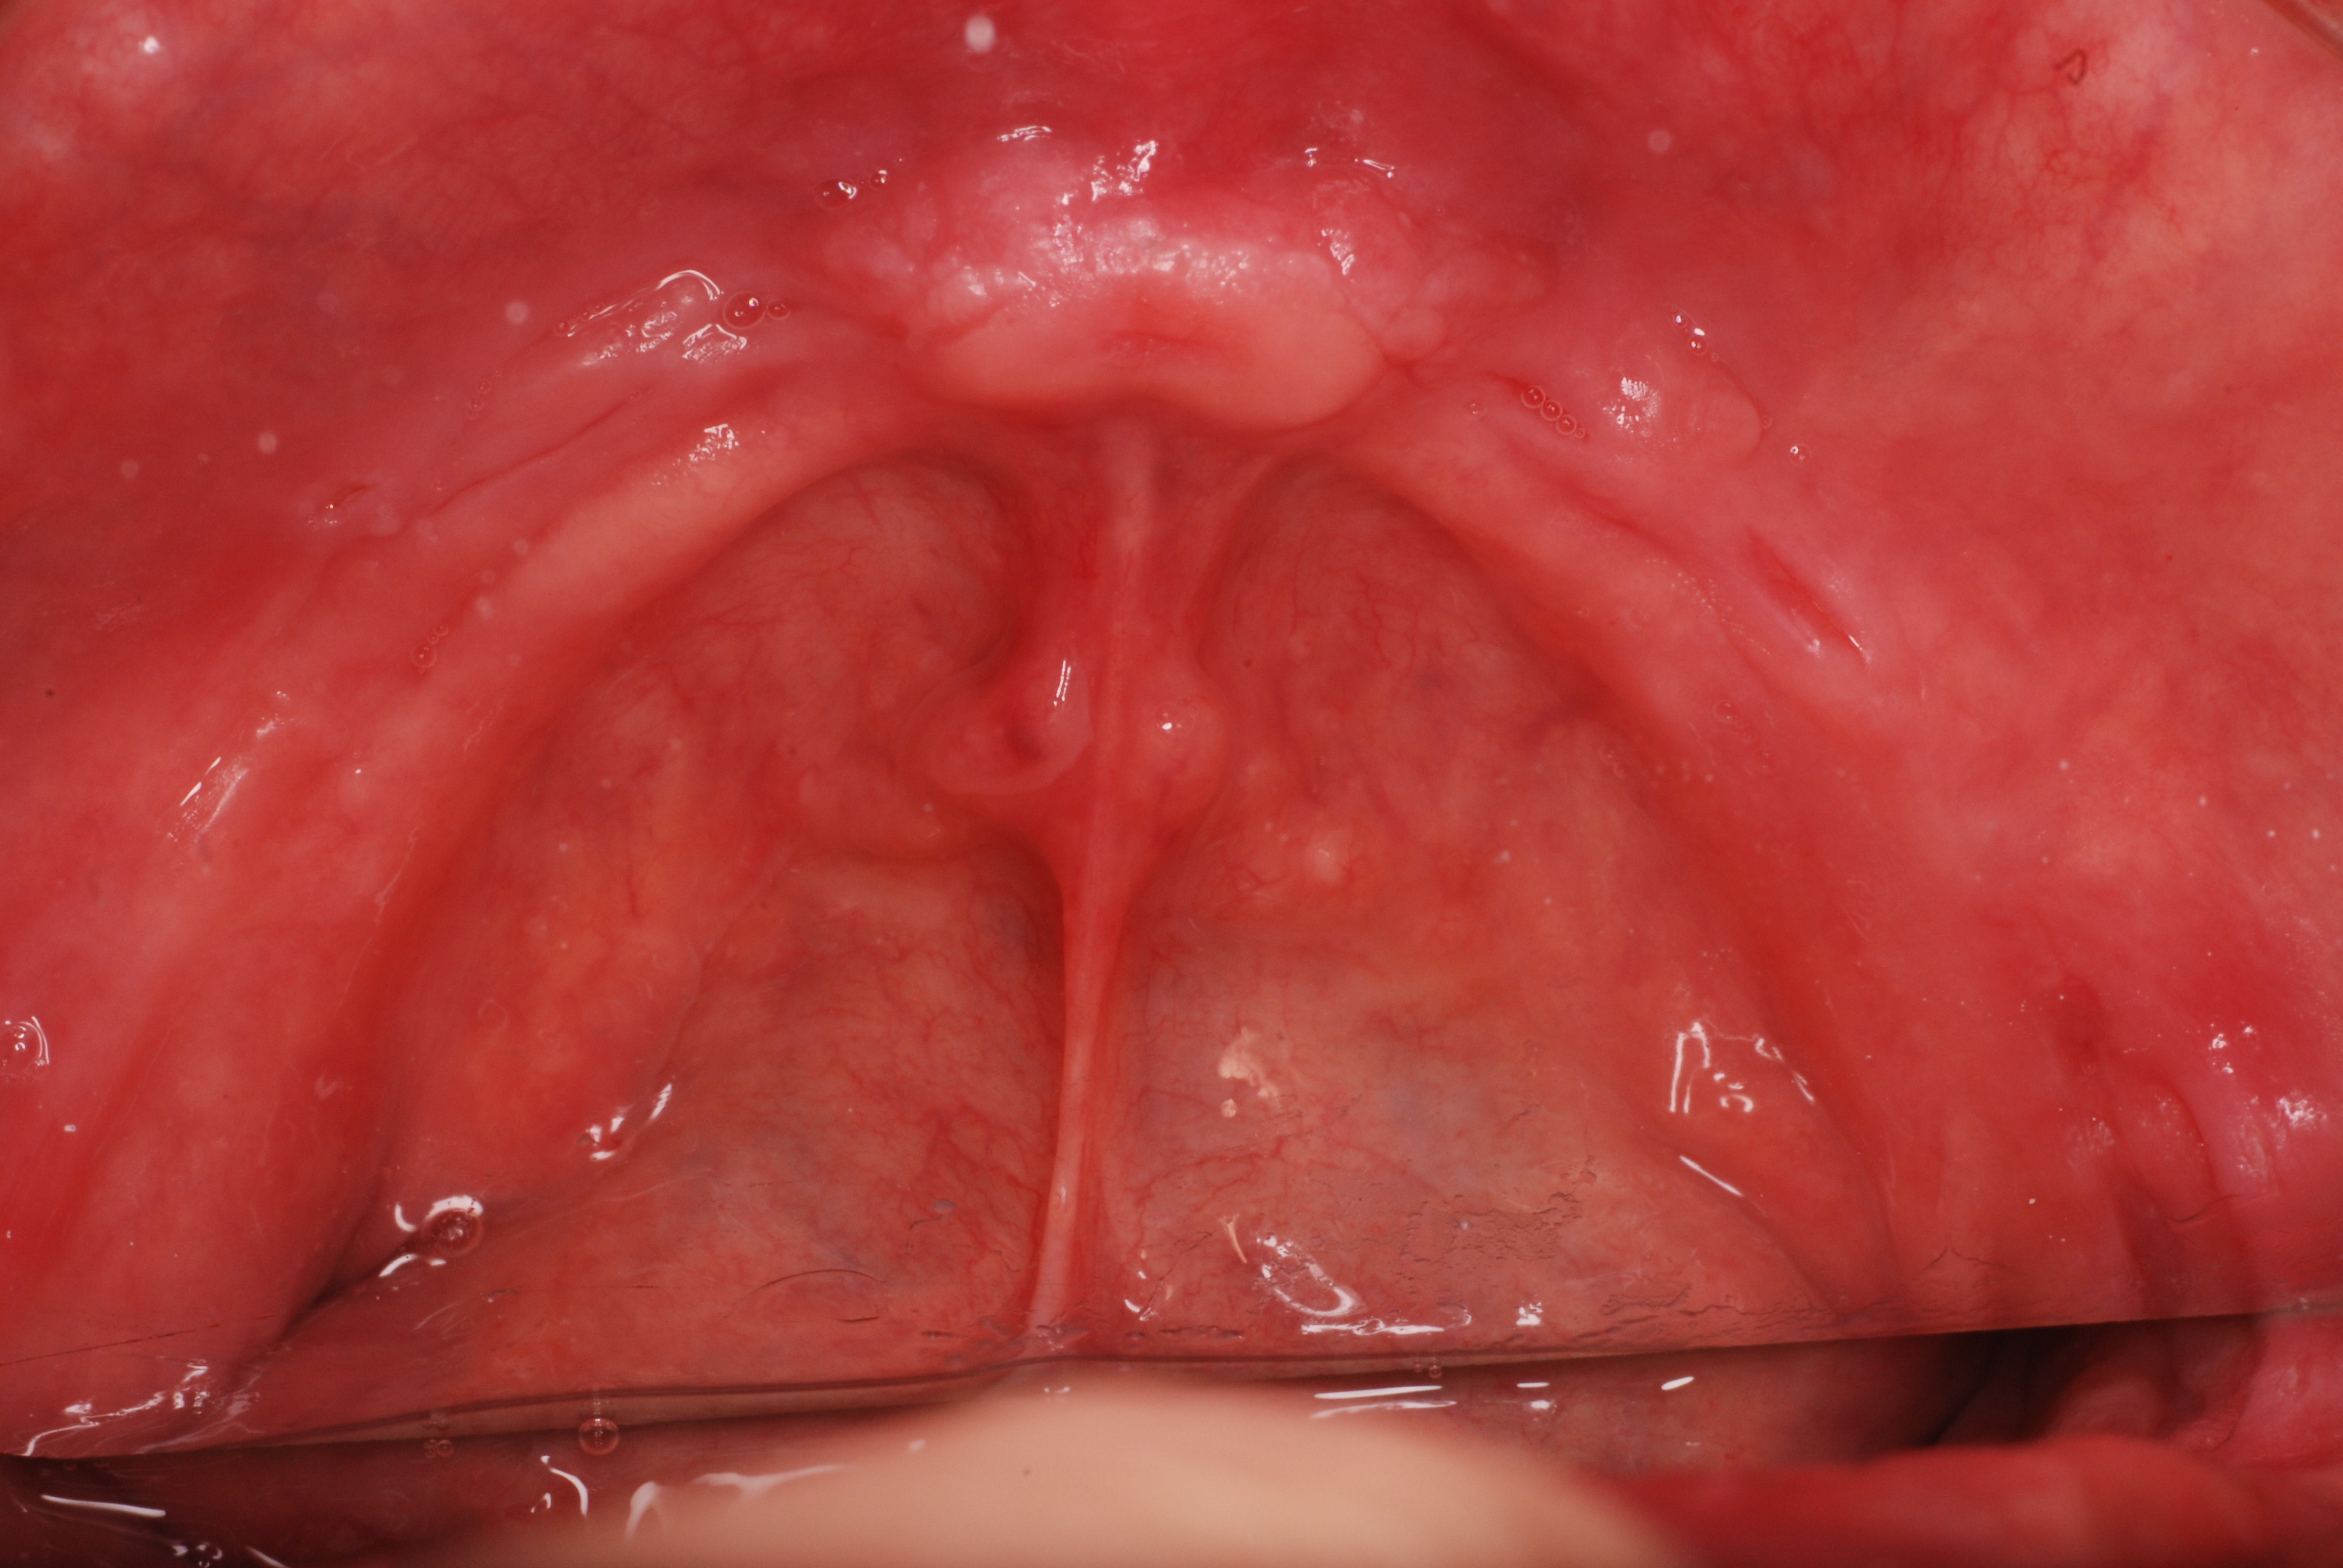

下記は上の歯が一本、そして

下の左側の奥歯分岐部に歯周病があります。

かなり重症ですね。

お口の中には高価なセトモノや金歯が多いのですが、

残念ながら健康になったわけではないのです。

分岐部の歯周病を見逃した為に頬が腫れあがり診察の結果、

歯の歯折か重症の分岐部の歯周病と判断した患者さんです。

検査の為に歯茎を開き少し悪いところを取って様子を見ていたのですが、又激痛が走りその為応急処置として東洋医学で対処しました。

ですが、根本的に悪いところを取らなくては再発するだけでなく歯そのものが駄目になる事をお話しして納得してもらい、セラミックを外しその後重症の分岐部の歯周病と判断して歯の一部分と悪い病気の歯肉をえぐりとったその後1週間後の写真です。

DSC_0012右上の奥から2番目の歯が問題の歯です。

セトモノが入っていますが、だからと言って健康になったわけではないのです。切り取った歯の残りと切り取り後が痛々しいですね。